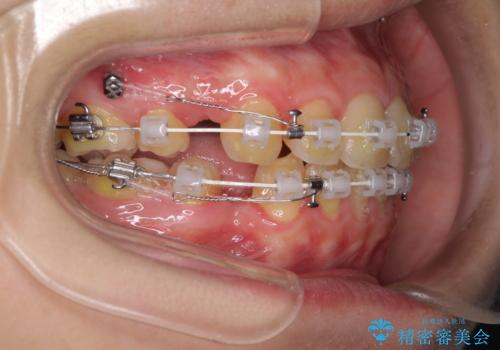

- 審美装置

- 2年3ヶ月

- 10-30回

口元を下げて口唇を閉じやすくする場合、抜歯矯正をお勧めさせていただくことが多いです。

治療前には必ず患者様とよく相談させていただき、どのようなゴールにするか、それにはどんな治療が必要かをご理解していただいたうえで、治療を開始いたします。